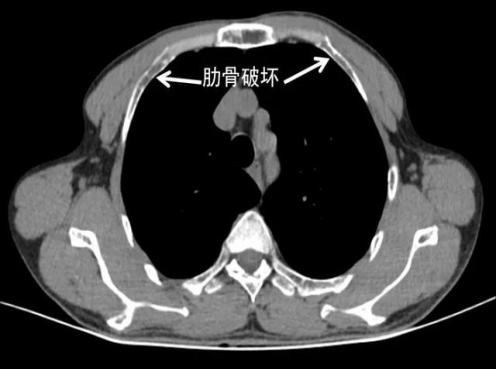

1

患者胸部外伤史明确,经过拍X线平片、CT等检查后,结果却是“肋骨未见明显骨折征象”;

2

过几天来复查时,可以看到肋骨骨折;

3

第一次检查报告某一根肋骨骨折,复查的时候变成三根或者四根肋骨骨折。